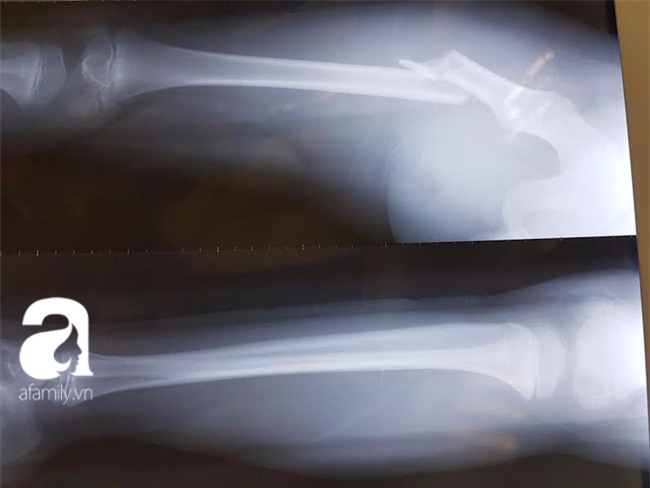

Kết quả chụp vết thương của cháu Kiên

Phim chụp X- Quang xương đùi cháu Kiên

Khi hai vợ chồng ông Dũng đến bệnh viện thì cháu Kiên đã được bác sĩ chiếu chụp X-quang và chẩn đoán là gẫy xương đùi phải. Sau khi được bó bột thì xương vẫn không khớp với nhau, vì vậy gia đình quyết định đưa cháu sang Bệnh viện Việt - Đức.

"Bác sĩ Tiến (Khoa chấn thương chỉnh hình 2) xác định trường hợp gãy chân như vậy của một cháu bé 7 tuổi là nặng và chỉ định bắt buộc phải mổ, nẹp vít xương. Con tôi tiếp tục được mổ vào ngày 3.12.2016, nằm điều trị tại Bệnh viện Việt Đức 5 ngày rồi ra viện để về nhà tiếp tục chăm sóc tại chỗ", ông Dũng viết trong đơn.

"Đánh giá chuyên môn của các bác sĩ là với chấn thương như của con tôi thì việc chạy và tự ngã mà không có tác động mạnh từ bên ngoài là điều khó có thể xảy ra. Mặt khác, cháu không có bệnh lý gì về xương, và xương đùi là nơi cứng nhất, rất khó gẫy, nếu không có lực rất mạnh tác động. Dự kiến cháu sẽ bị ảnh hưởng không nhỏ đến việc sinh hoạt bình thường trong một thời gian dài", theo đơn thư.